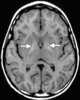

Pantothenate kinase-associated neurodegeneration (PKAN), formerly called Hallervorden–Spatz syndrome, is a genetic degenerative disease of the brain that can lead to parkinsonism, dystonia, dementia, and ultimately death. Neurodegeneration in PKAN is accompanied by an excess of iron that progressively builds up in the brain. [Source: Wikipedia